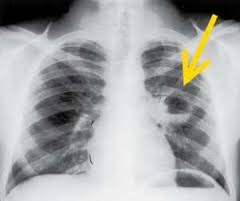

Абсцесс легкого - лечение в Финляндии

Абсцесс легких является патологическим процессом, характеризующимся сформировавшейся в легочных тканях ограниченной полостью, которую вызвал некроз и последующее гнойное расплавление.

Абсцесс легкогоДля установления безошибочного диагноза, определения широты патологии назначают выполнение: